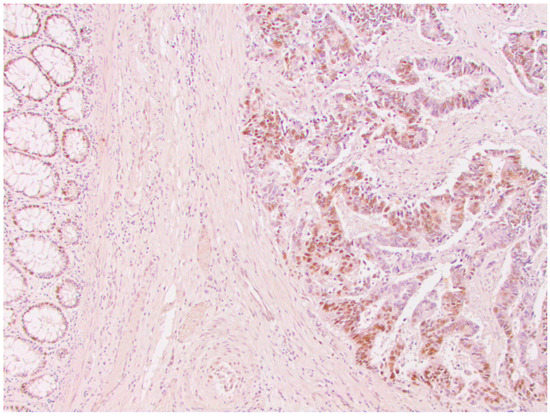

From a total of 104 patients with colorectal cancer, immunohistochemical analysis of the expression of all four MMR proteins showed that heterogeneous expression of MMR proteins (as well as deficient immunoreactivity of tumor cells (Figure 1) was present in 12 cases, while proficient expression of MMR proteins was detected in 80 tumors (Figure 2). Heterogeneous expression of PMS2 protein and heterodimeric pair MLH1/PMS2 was found in two tumors, MSH2/MSH6 was found in seven tumors (two of which also showed heterogeneity for MLH1/PMS2) and MSH6 was found only in one tumor. In seven out of twelve tumors micromorphologically, both forms of heterogeneous protein expression coexisted in the tumor tissue as intraglandular and zonal heterogeneity (Figure 3). Isolated intraglandular heterogeneous protein expression was found in two tumors (Figure 4), while zonal heterogeneity was present in three tumors (Figure 5).

Figure 2. Proficient nuclear expression of MSH2 protein in colorectal cancer, ×100.

Figure 3. Zonal and intraglandular distribution of heterogeneous nuclear expression of MLH1 protein in colorectal cancer, ×100.